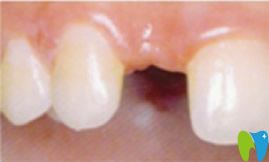

牙齒種植前:

到后,我拍了一張牙齒的全景CT ,醫(yī)生建議我做種植牙。因?yàn)榉N植牙技術(shù)提取的是自體骨骼組織,與種植體完美融合。該技術(shù)適應(yīng)于所有缺牙患者,并且萬(wàn)翔口腔種植牙手術(shù)設(shè)計(jì)過(guò)程完全“可視”,治療過(guò)程微創(chuàng)、精準(zhǔn)、快速、安全,種植后的牙齒可以媲美真牙,效果也很長(zhǎng)久。